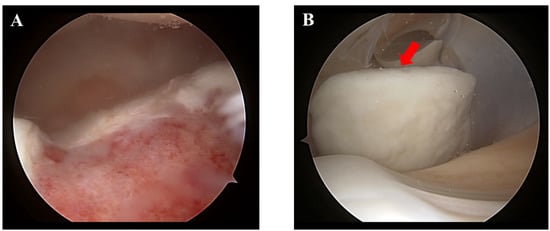

2. Case Presentation